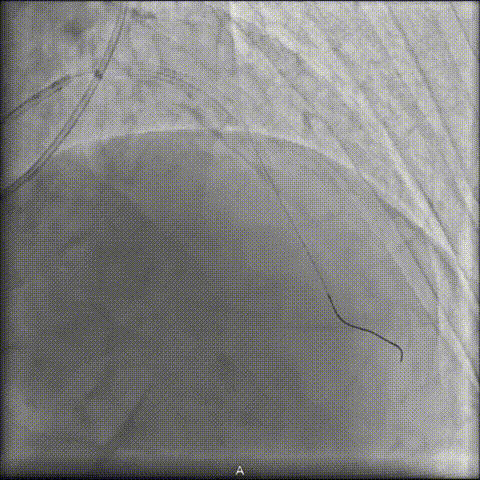

后续NC球囊扩张充分,支架植入顺利。

术后OCT确认支架膨胀充分,贴壁良好。造影提示无残余狭窄,TIMI血流Ⅲ级。